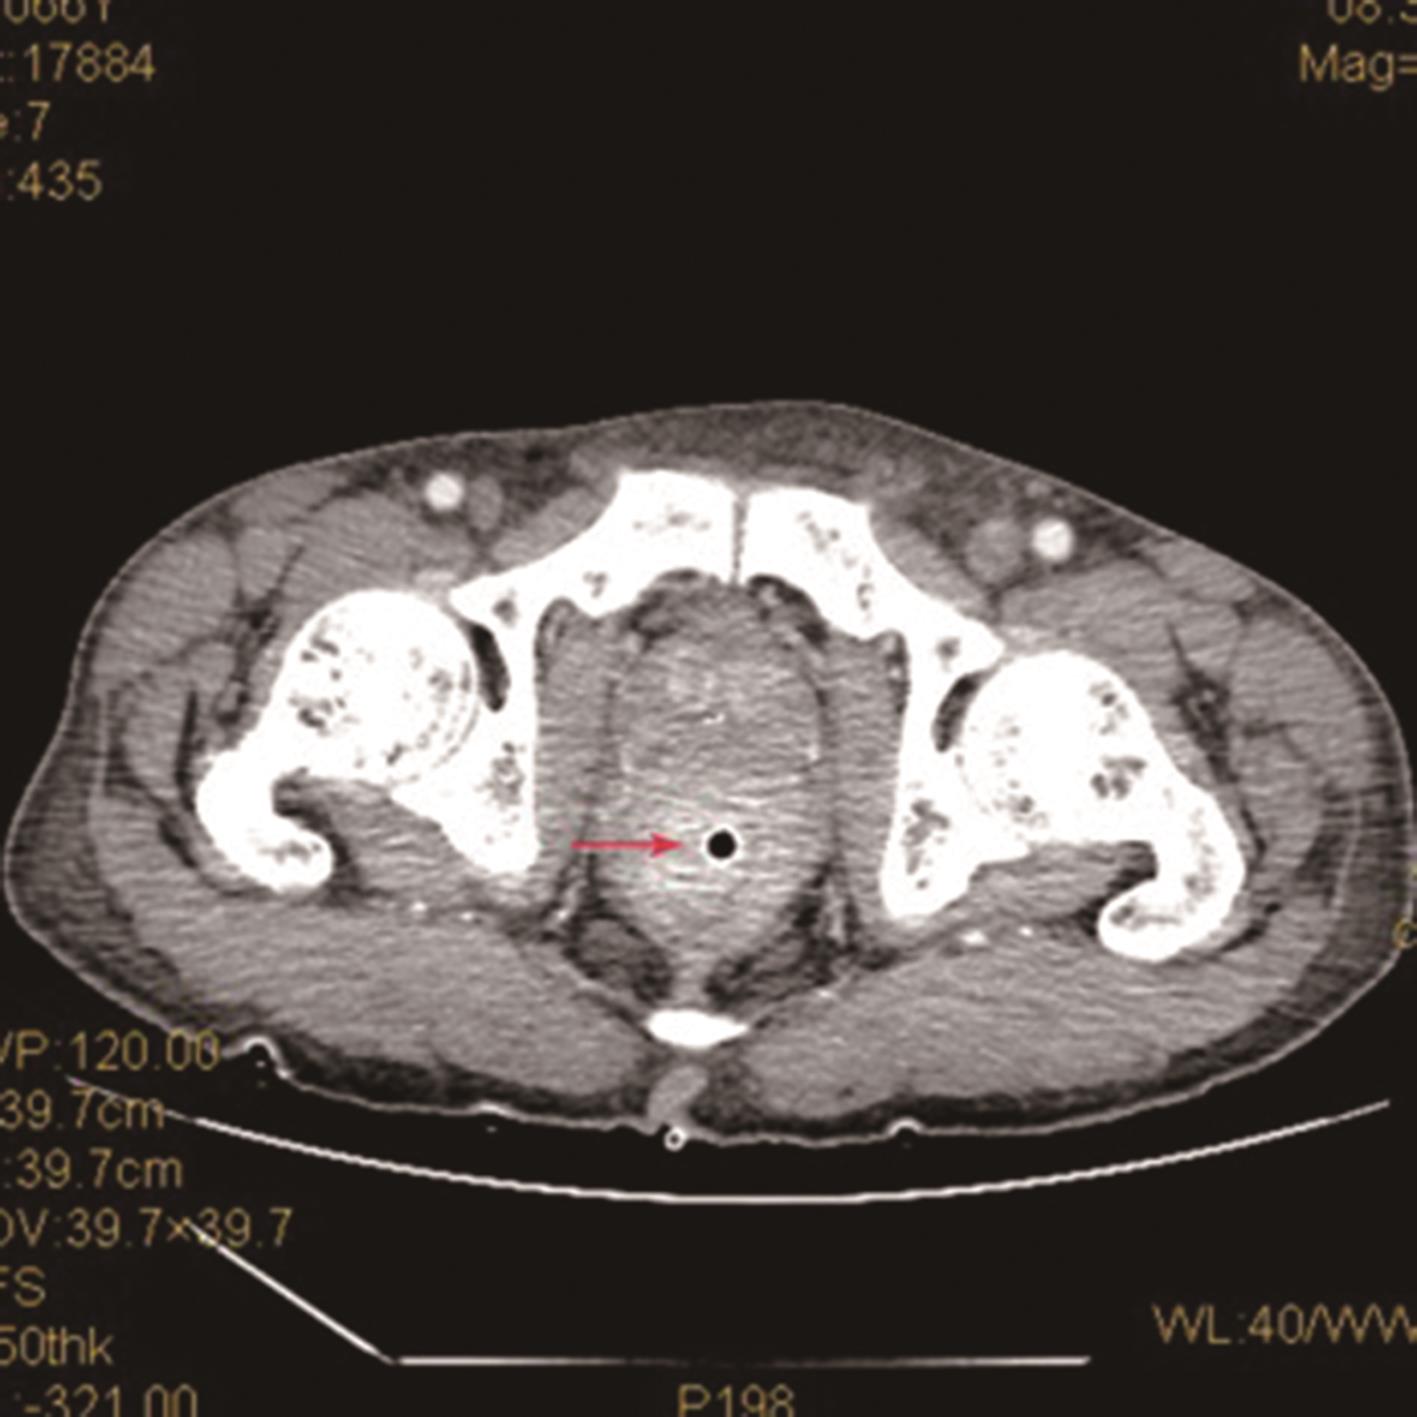

• MTAP在前列腺癌中的表达及对免疫细胞的影响初探

2024, 49(2):222-230. DOI: 10.13406/j.cnki.cyxb.003429

摘要 (67) HTML (47) PDF 7.36 M (96) 评论 (0) 收藏

摘要:目的 探究甲硫腺苷磷酸化酶(methylthioadenosine phosphorylase,MTAP)在前列腺癌不同临床阶段的表达差异及其对免疫细胞的影响。方法 从TCGA和GTEx数据库中获取MTAP的表达谱数据,利用生物信息学方法进行泛癌分析。免疫组化验证上述结论并探究MTAP与临床病理指标之间的关联。RT-qPCR和Western blot检测MTAP在不同前列腺癌细胞系中的表达水平,分析MTAP与肿瘤恶性程度之间的关联。生物信息学方法分析前列腺癌中MTAP与免疫细胞的关联并进行免疫组化验证。结果 在前列腺癌中,MTAP的表达在肿瘤发生早期升高后逐渐降低,与T分期和Gleason评分呈负相关(rs=-0.576,P=0.000,rs=-0.284,P=0.020)。MTAP与多种免疫细胞存在相关关系,其中MTAP与CD4+T细胞呈正相关(r=0.643,P=0.000),与NK CD56bright细胞呈负相关(r=-0.570,P=0.000)。结论 前列腺癌中,MTAP的表达呈现早期升高后逐渐下降的趋势,与T分期和Gleason评分呈负相关。MTAP对免疫细胞的浸润和细胞功能的发挥有调节作用,是一种潜在的生物学标志物和免疫治疗靶点。

• 0+1

• 1+1

• 2+1

• 3+1